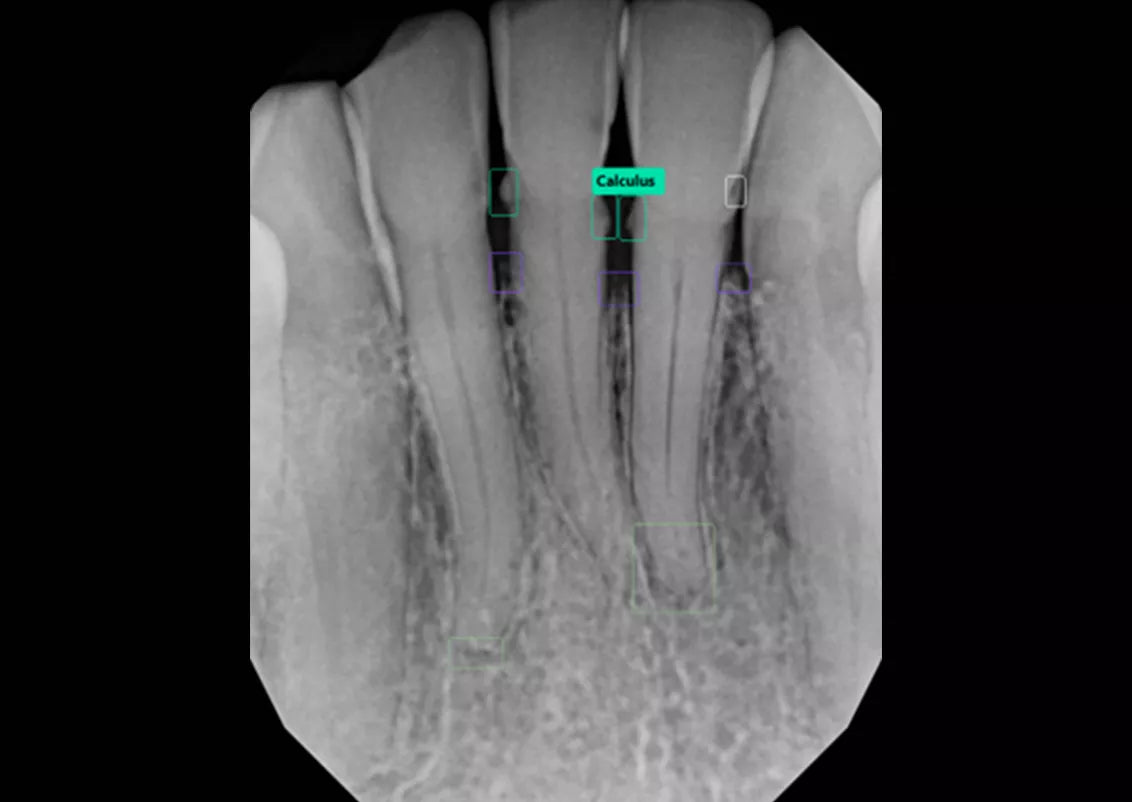

Built into DEXIS™ Imaging Suite Software, the DEXassist Solution provides assisted intelligence with a single click. This new solution enables users to identify up to six dental findings on 2D x-ray images.

The DEXassist Solution integrates AI features from DTX Studio™ Clinic into DEXIS Imaging Suite Software.